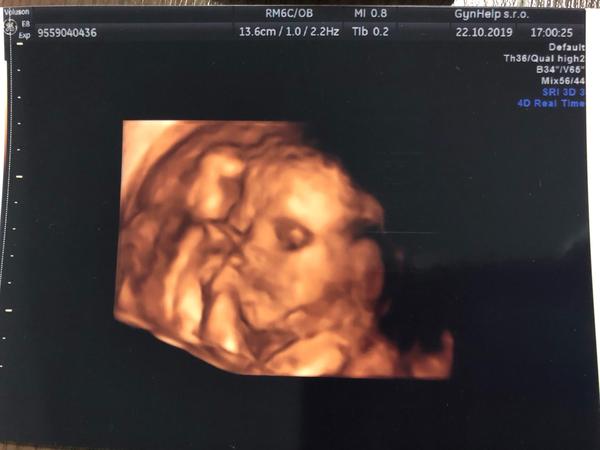

Ahoj zkus si zajít na 3D/4d utz. Tam jsme dostali i x fotek s pytlem. 😂 Jinak ve 13 tt mi řekli ze je to kluk jen na 60% v 18tt na 100% tam se ukázal i s nářadím a 22 tt 2. Screening to same a 25tt jsme si došli jen tak jako samoplatci na to 3D a to bylo moc fajn. Půl hodina, všechno nám doktor ukázal, všechno natáčel a bylo to moc moc hezké. Tohle opravdu doporucuju, protože tam ten dr má fakt čas to zkoumat a tak.

@lucinkafialova kindr s překvapením to je hezké přirovnání. 😂❤️ Jinak bych se nebala oni se fakt moc snaží, doporucuju na Hostivaři Gynhelp venoval se nám, všechno ukazoval, nás teda měl hlavu v placente tak mi trasl břichem ať nám ukáže taky obličej 🤣 ale sám říkal já se dostanu všude nic nám nezůstane skryto. 😁

@95newmommy2020 jeee to je krasny 😍❤ takovy koblizek malej zkusim to a uvidime ale i tak ja jsem rada ze budeme mit i tu holcicku po tom vsem cim jsem si prosla je to nas malej zazrak ❤ no tak se vam nechtel ukazat aby jste nekoukali na nej 😂😁

Jinak nám prave ukazoval pohlaví hodně dobře, ale ten obličej to byl problém. 😁